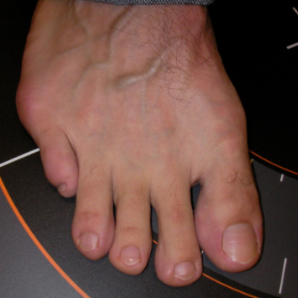

Juanete de Sastre

Juanete de Sastre: antes Juanete de Sastre: después